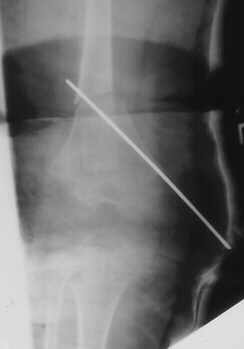

Osteotomies about the knee can be done in order to correct alignment.

Varus osteotomy of the femur should be avoided, as these people tend

to develop a varus deformity and incongruity as a result of this dysplasia.